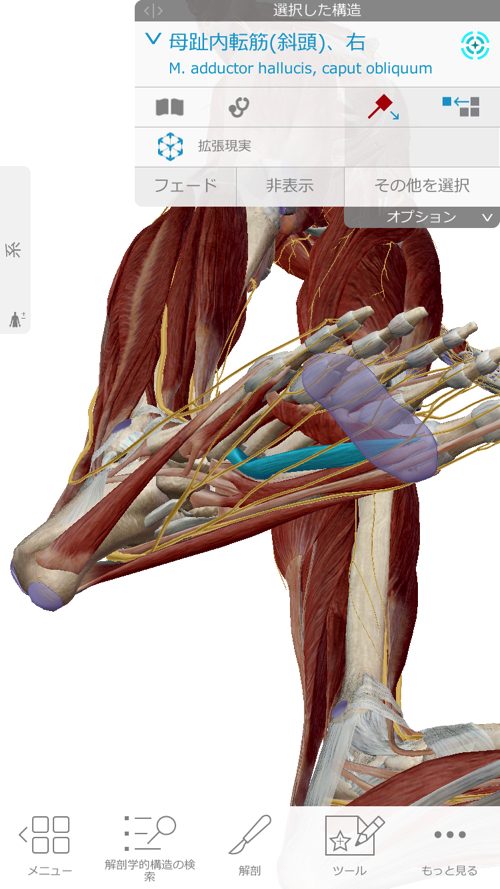

さらに膝に出来た余裕を利用してこの長腓骨筋を緩めて調整します。

今回、特にしっかりと調整したのはこの長腓骨筋です。

それは何故かというと・・

長腓骨筋は足裏からクルブシを通って膝の方へ繋がっていきます。

腓骨筋の先には親指を動かす短母趾屈筋

同じく趾に影響の大きい母趾内転筋にも連携しています。

長腓骨筋は膝・足首・足裏・足の指に全て影響するのがお分かり頂けたと思いますが

足だけ、膝だけ・腰だけと部分部分で切り取った見方では、脚全体の硬直や捩れ、微妙なズレなどは絶対に分からないし、レントゲンやMRIには、この長腓骨筋などの硬直やヨジレは写らないのです。